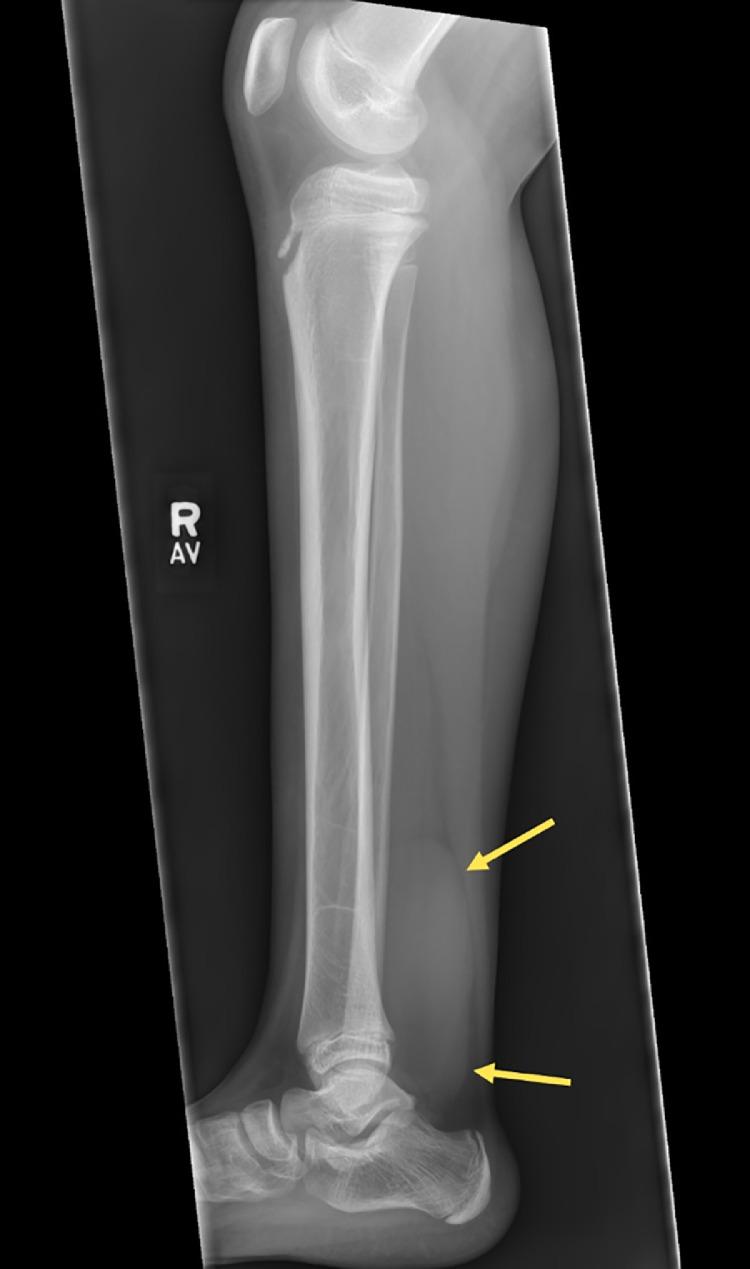

Pigmented villonodular synovitis is an uncommon benign neoplastic proliferation associated with the synovium, bursa, or tendon sheaths; most commonly occurring in the third to fourth decade of life. It is rare in children and may be painful or painless. Magnetic resonance imaging is the diagnostic study of choice. In this report, the radiologic, ultrasound, and magnetic resonance imaging findings of pigmented villonodular synovitis of the flexor hallucis longus in a 12-year-old girl are discussed. We briefly review the surgical findings as well. To our knowledge, this is the first case report that simultaneously synthesizes the imaging findings of 3 diagnostic imaging modalities for optimal visualization and is the youngest reported case of pigmented villonodular synovitis of the flexor hallucis longus tendon.

色素沉着绒毛结节性滑膜炎是一种罕见的与滑膜、滑囊或腱鞘相关的良性肿瘤性增生;最常发生于人生的第三个至第四个十年。在儿童中罕见,可能有疼痛或无痛。磁共振成像(MRI)是首选的诊断检查方法。在本报告中,讨论了一名12岁女孩拇长屈肌色素沉着绒毛结节性滑膜炎的放射学、超声和磁共振成像表现。我们也简要回顾了手术所见。据我们所知,这是第一例同时综合三种诊断成像方式的影像学表现以实现最佳可视化的病例报告,也是已报道的最年轻的拇长屈肌腱色素沉着绒毛结节性滑膜炎病例。